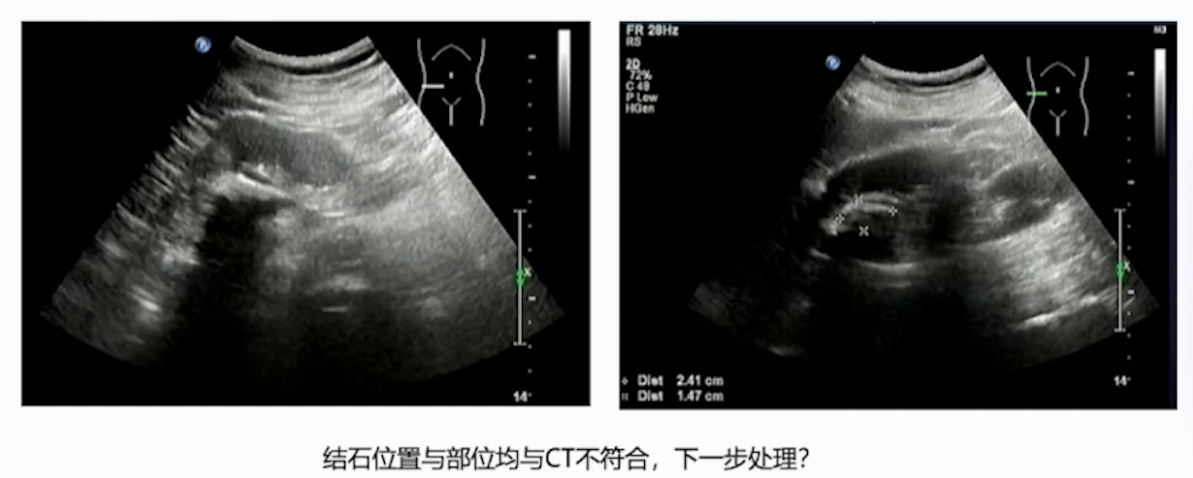

术前B超显示:右肾上盏有一颗21mm×30mm的大结石,与CT所见不符。

患者有右侧肾部分切除术病史,CT提示的结石大小与术中实际发现不一致,超声检查结果与实际结石负荷更吻合;术后结石成分分析确诊为氰基丙烯酸酯,该成分与患者肾部分切除术中用于止血、减少尿外渗的粘合剂相关,属于临床罕见结石类型。

本例患者诊疗的关键难点在于,其一是术前影像学评估存在偏差,CT虽为结石检查的“金标准”,但本例中未能准确反映结石实际大小,需警惕特殊病史患者的检查局限性;其二是结石处理难度大,该类粘合剂成分结石质地坚硬,软镜下激光碎石难以奏效,最终通过经皮肾镜直接击碎取出,提示特殊成分结石需针对性选择手术方式。

针对有肾脏手术史等特殊病史的患者,术前检查不可单一依赖CT,应采用“超声+IVP+CT平扫”或“超声+CTU”的联合检查方案,整合不同检查的优势,全面获取结石大小、位置等信息。在进行肾部分切除术时应注意操作规范,术中若集合系统存在较大破裂,需采用 “两层缝合” 技术(细针线缝合集合系统 + 肾实质外层缝合),谨慎使用氰基丙烯酸酯类粘合剂,避免粘合剂渗入集合系统,为后续结石形成埋下隐患。此外,结石成分是追溯病因的关键,尤其对于罕见结石,若未进行成分分析,难以发现氰基丙烯酸酯这类特殊成因,因此有条件的医疗中心应将结石成分分析纳入术后规范流程,为病因诊断和后续预防提供依据。